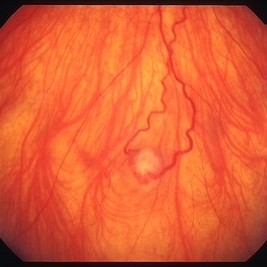

Retinal capillary hemangiomas 3

Jan 11 2013 by Alex P. Hunyor, MD

Retinal capillary haemangiomas, left superior periphery, in a 20 year old female with von Hippel-Lindau disease.

Condition/keywords: hemangioma, retinal capillary hemangioma, Von Hippel-Lindau